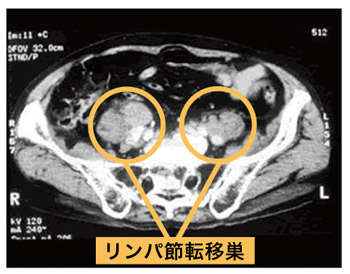

CT

CTは高速に回転するレントゲン装置の中に入って体の断面画像を撮影する検査で、がんのリンパ節への転移や周辺組織への広がり(浸潤)などを調べるために行います。